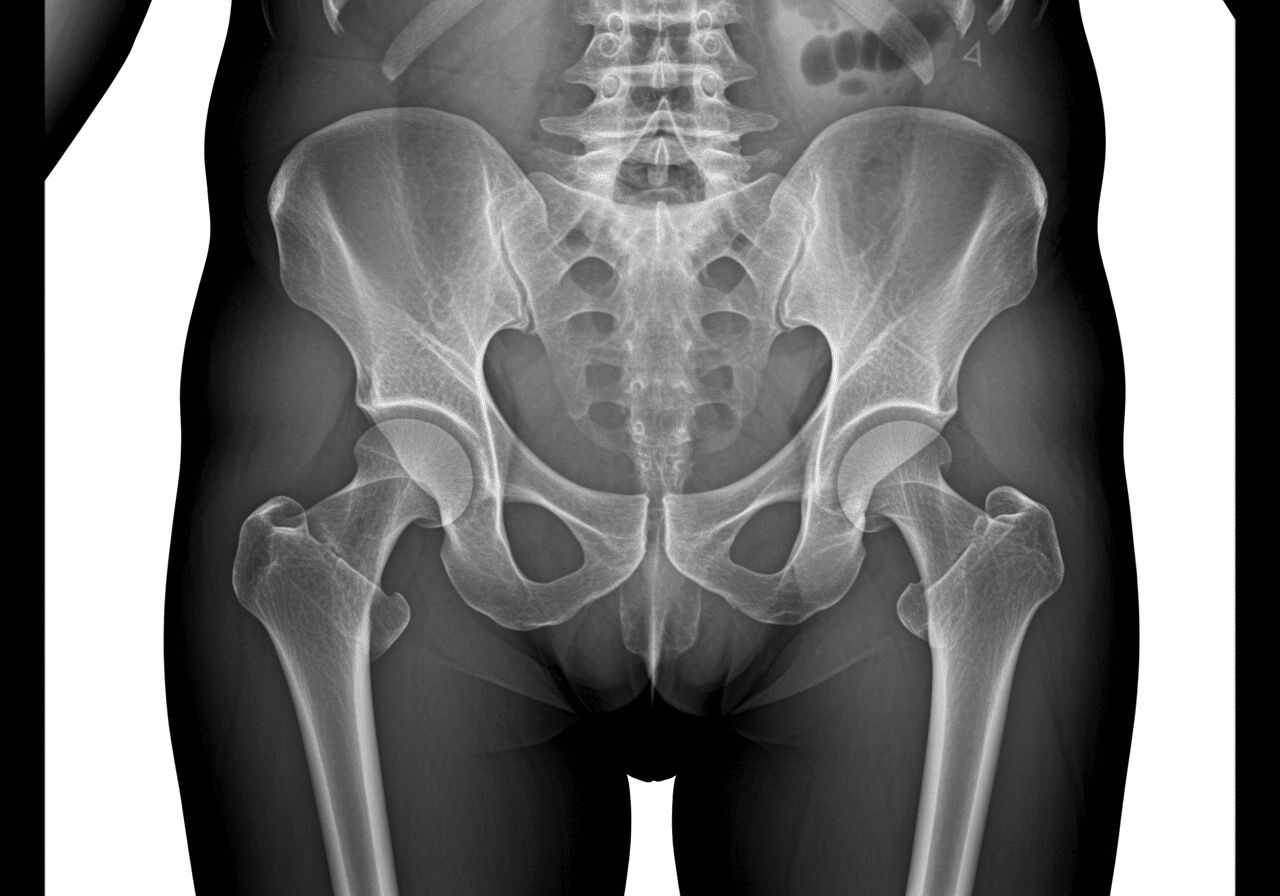

Unlike traditional urgent care centers that completely lack hip fracture management capabilities or close at 8 PM, Priority ER operates 24/7 emergency services with immediate access to digital x-ray imaging, CT scanning for complex pelvic fractures, and board-certified physician-initiated stabilization protocols within the critical first hour. Our COLA-certified diagnostic imaging[4] ensures accurate fracture classification using Garden and AO/OTA systems while our direct trauma surgeon and orthopedic consultation ensures seamless coordination when surgical fixation becomes necessary for displaced hip fractures or unstable pelvic injuries requiring emergency operative intervention.

According to the American Academy of Orthopaedic Surgeons, approximately 300,000 hip fractures occur annually in the United States, with femoral neck fractures comprising 45%, intertrochanteric fractures 45%, and subtrochanteric fractures 10%[5]. The critical difference between survival and death often comes down to seeking appropriate pelvic and hip fractures care within the first 6 hours of injury, particularly for elderly patients where delayed surgical treatment increases 30-day mortality by 41%[6]. Our trauma emergency capabilities include immediate pelvic binder application for unstable pelvic fractures, massive transfusion protocols for hemorrhagic shock, and urgent transfer coordination when patients require level-1 trauma center resources beyond emergency stabilization.

Priority ER's diagnostic capabilities for pelvic and hip fractures exceed Joint Commission standards for emergency departments[14], featuring advanced digital radiography systems plus CT scanning with IV contrast providing immediate identification of femoral neck fractures, intertrochanteric fractures, and pelvic ring disruptions requiring emergency surgical intervention. Our emergency physicians trained in Garden classification (Types I-IV for femoral neck fractures based on displacement and alignment), AO/OTA classification for complex fractures, and Young-Burgess classification for pelvic ring injuries ensure accurate assessment guiding life-saving treatment decisions[15]. The integration of massive transfusion protocols, pelvic binder application, and Buck's traction stabilization prevents complications that delayed treatment causes including hemorrhagic shock, fat embolism, and avascular necrosis.

Advanced imaging through our comprehensive diagnostic capabilities provides CT angiography assessing vascular injury in pelvic fractures, MRI identifying occult hip fractures when plain x-rays appear normal despite clinical suspicion, and repeat imaging protocols monitoring displacement ensuring fracture stability during emergency department observation. For elderly patients, our emergency physicians perform comprehensive medical optimization including cardiac clearance, anticoagulation reversal when necessary, and metabolic panel assessment identifying electrolyte abnormalities and anemia requiring correction before surgery. This comprehensive approach explains why the American College of Emergency Physicians mandates emergency department evaluation for all hip fractures, with zero exceptions allowing urgent care treatment of these life-threatening injuries.